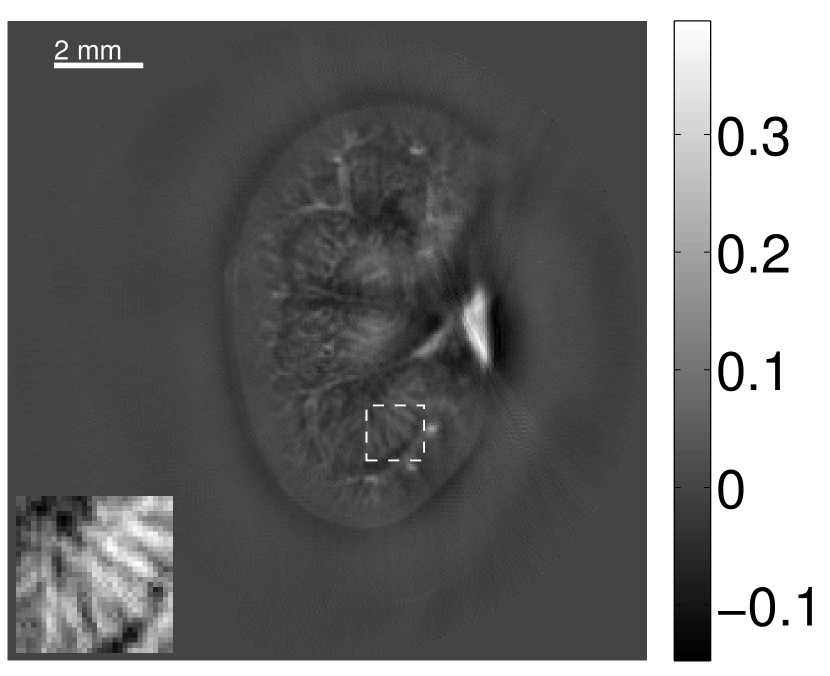

VI-E Results: kidney phantom

The images and EIRs reconstructed by use of the VP algorithm that was based on the 2D imaging model that neglected the SIR are shown in Figures 15 and 16. The latter figure contains results corresponding to different values for the regularization parameter . From Fig. 15, it can be observed that use of the conventional iterative method that utilized the measured EIR resulted in distortions and loss of details in the reconstructed images. Use of the VP algorithm improved the contrast and the details in the reconstructed images (Fig. 15(c) and 16(a)). Furthermore, the images reconstructed by use of the VP algorithm had a more uniform background.

In Figure 17, the results corresponding to use of the 3D imaging model that incorporated SIR effects are shown. The EIR estimated by the VP algorithm is also shown. In Figure 18, images and EIRs reconstructed by use of the VP algorithm with different regularization parameters values are shown.

Similar to the case described above where the transducer SIR was neglected, these results reveal that use of the VP algorithm can produce images with a cleaner background and enhanced spatial resolution than yielded by use of a conventional iterative algorithm that employed the measured EIR. For example, detailed information regarding the vessels near the organ’s periphery was better preserved by the VP algorithm than by the conventional iterative algorithm. These images corroborate our assertion that the VP algorithm can significantly reduce the artifacts and distortions in the reconstructed image. It is also worth pointing out that, unlike the numerical phantom studies, the artifacts and distortions in the images may be caused not only by the inaccurate EIR but also by other factors, such as neglecting acoustic heterogeneities and the variation of the EIRs among the elements of the transducer array. In such cases, the EIR estimated by the VP algorithm represents an effective system impulse response that minimizes the inconsistency between the measured data and the imaging model.